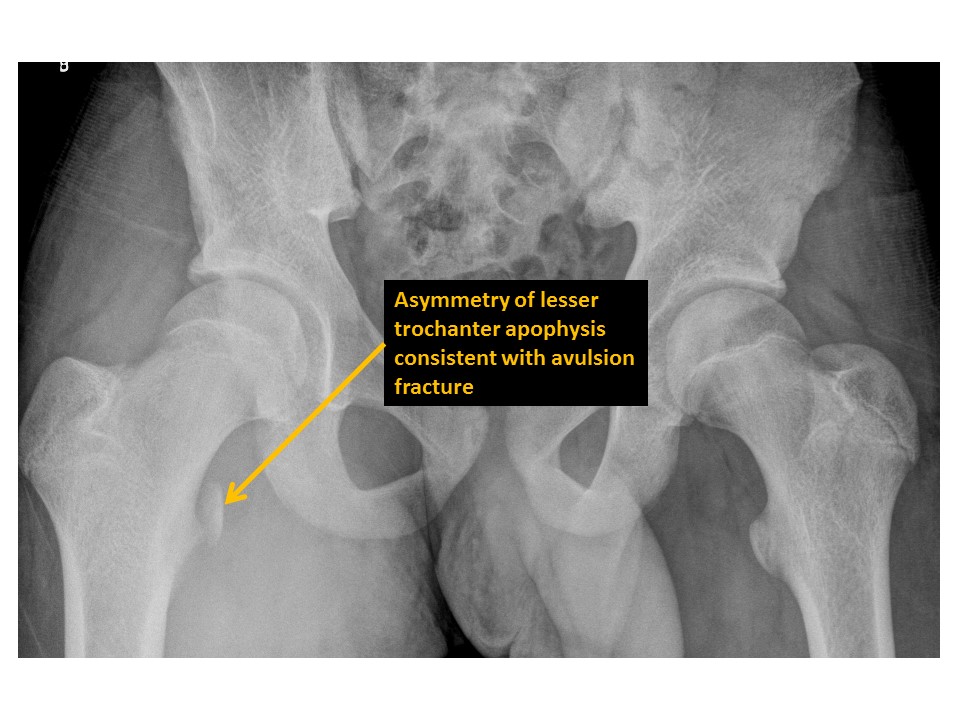

There are avulsion fractures of the greater or lesser trochanters. [Yes/No]